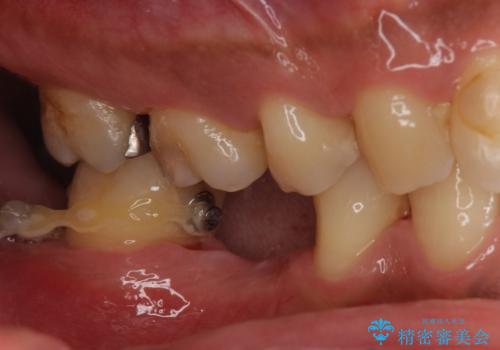

- 昔、治療された銀歯が気にな流ということを主訴で来院された患者様です。

銀歯を外し、虫歯治療を行い、セラミックインレーにて治療しました。

銀歯を除去し、虫歯をとって、セラミックインレーにて治療を行いました。